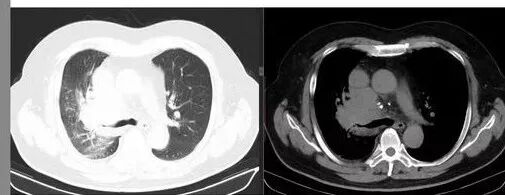

肺门及纵隔多发淋巴结。2L,4R,3区都有肿大淋巴结。

南边:有老师认为,血管前的这个应该是一个胸腺来源的。我觉得不是,为什么不符合胸腺来源呢,就看那个内乳动脉

双侧对比:右侧增粗,提示供血

但在内侧,不是外移

所以我倾向于淋巴结可能

胸腺瘤按理推压外移的多

而且胸腺癌转移不以淋巴结为主,如果淋巴结显著,按理周围侵袭性比较强,淋巴结也应该以附近为主,不应该以肺门为主,不符合引流规律。

支气管狭窄,壁有侵犯

局限性中央间质增厚,考虑癌性淋巴管炎